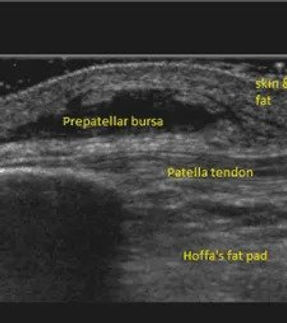

Mr Stapleton is an extended scope Podiatrist which includes Prescription only Medicine, Corticosteroid, hyaluronic acid and local anaesthetic injection therapy, shock wave therapy, nail and skin surgery and ultrasound imaging, with interest biomechanics and orthoses prescription.